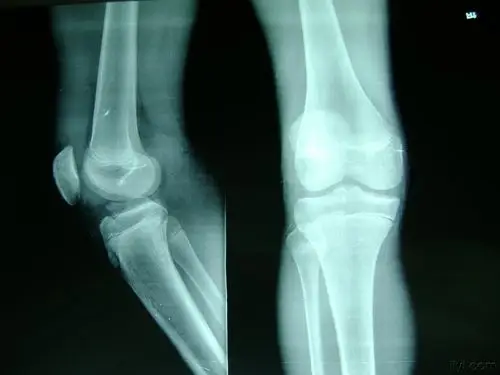

双侧桡骨远端粉碎性骨折闭合复位

胫骨平台骨骺粉碎性骨折 1.jpg